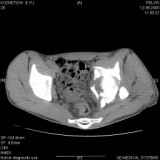

Уважаемые коллеги! Хотелось бы услышать совет по тактике лечения представлленого больного.Поступил после лечения в одном изотделений области. Травма 2,5 месяца назад. После выведенияиз шока был произведен остеосинтез перелома бедра, предплечья, до перевода к нам проводилосьвытяжение по оси шейки бедра за стержень, введенный в большой вертел. На сегодня деформацияригидна, клинически мобильности не определяется. Заранее признателен. P.S. Данный вид травм не включен в перечень "высокотехнологичных операций", направить длялечения по квотам Минздрава очень сложно.

Привет, Леонид. Оскольчатый высокий двухколонный перелом в такие сроки трогать не надо, т.к. это про такие переломы сказано: "кто с ножом на Ж. пойдет тот в ней и останется...".

Может быть неплохой результат при консервативном лечении и ранних движениях.

Если заболит после начала нагрузки в 4-6 месяцев - эндопротез.

Спасибо за отклики. Мы решили также пока занять выжидательную тактику, позднее решать вопрос об

артропластике.